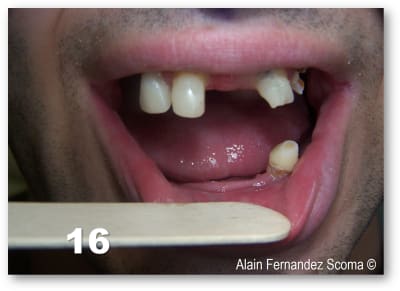

Tu ne peux pas savoir ? Ce n’est pas une surprise, rien qu’à voir les muqueuses, on devine que ce sont des crêtes flottantes en haut et qu’il n’y a pas suffisamment de gencive attachée en bas.

Olieve des crêtes flottantes sont sûrement une contre indication pour une chirurgie guidé flapless mais pas pour un guide à appuis osseux. Un exemple de notre ami béotien sur une patiente édenté total (9) après plusieurs années de port d'une prothèse amovible (10) usée la gencive est flottante. Le guide à appuis osseux a une position stable est précise (11). En fin de chirurgie le bridge à armature métallique rigide est mise en place mettant en charge les implants pour que la patiente retrouver immédiatement la fonction et l'esthétique (13). 8 mois après (14) le bridge est retiré pour vérifier l'ostéo-intégration des implants. La levé du lambeau a permis de positionner favorablement le conjonctif guidé par la prothèse pour la conformée.